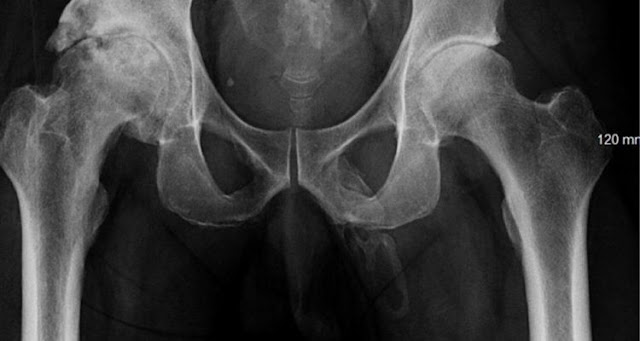

The doctors found this case extremely rare when they performed a radiograph of the pelvis, in order to look for signs of bone fracture. But instead, they spotted a bone-like calcification in a most unexpected place ...

Calcium salts have accumulated in soft tissues and have hardened to form an "extended plaque" along the penis stem, as you can see on the radiograph below: